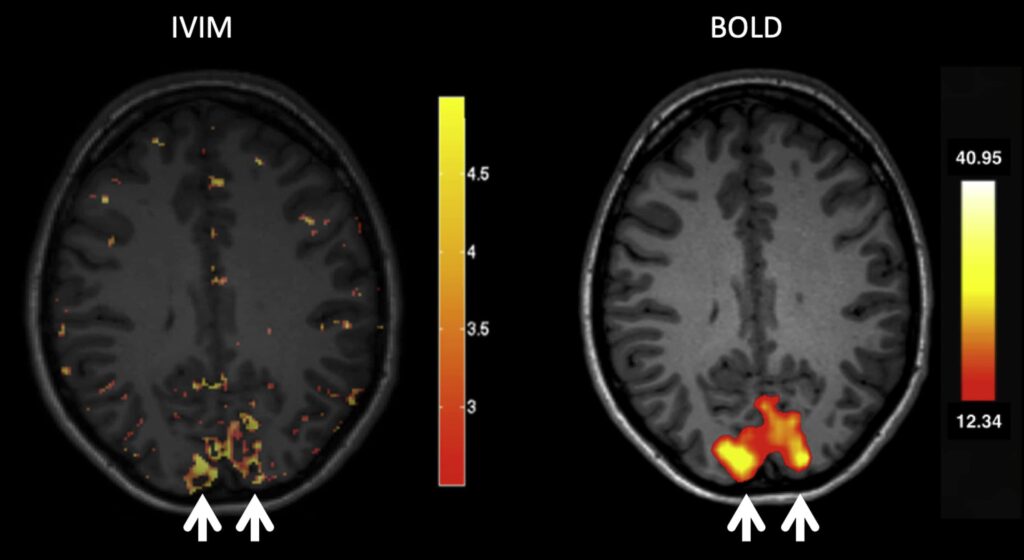

IVIM (Intravoxel Incoherent Motion) is a specialized MRI technique that helps to measure both tissue diffusion and microvascular perfusion. It is especially useful in areas such as oncology, liver disease assessments, and other diagnostic procedures where traditional imaging techniques might fall short. This method gives clinicians a more detailed insight into what’s happening at the cellular level.

IVIM imaging plays a critical role in diagnosing and treating complex health conditions. By offering clearer insights into tissue health and microcirculation, it helps medical professionals to diagnose diseases more accurately, track progression, and tailor treatments accordingly. It is particularly beneficial in oncology for tumor characterization, as well as in evaluating liver function and other organ-specific conditions.